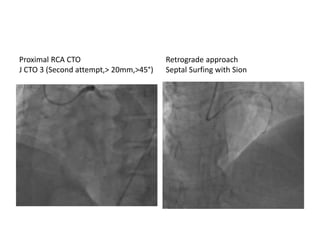

Proximal RCA CTO

J CTO 3 (Second attempt,> 20mm,>45°)

Retrograde approach

Septal Surfing with Sion

Proximal RCA CTO JCTO 3 (Second attempt,> 20mm,>45°) Retrograde approach Septal Surfing with Sion